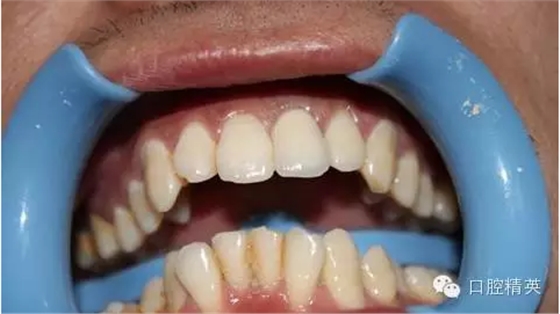

7:試戴烤瓷牙,鈷鉻瓷牙,瓷肩臺(tái)處理

8:頸緣檢查

9:完全就位

10:黏結(jié)后,側(cè)面觀

11:正面微笑圖